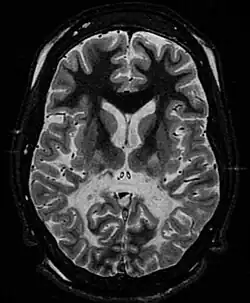

Les leucodystrophies sont des maladies rares caractérisées par un processus de démyélinisation du système nerveux central et périphérique, d'apparence primitive et non inflammatoire et aboutissant à une sclérose cérébrale. Ce sont presque exclusivement des maladies génétiques.

Le terme de leucodystrophie se rapporte à un groupe de maladies d'origine génétique affectant la myéline du système nerveux central. La myéline constitue la substance blanche du cerveau et de la moelle épinière. Elle enveloppe la fibre nerveuse de la même manière que l'isolant plastique d'un câble électrique : c'est elle qui permet la bonne conduction des messages nerveux. Dans les leucodystrophies, cette myéline peut avoir des problèmes pour se former ou pour se maintenir (parfois, on remarque une démyélinisation).